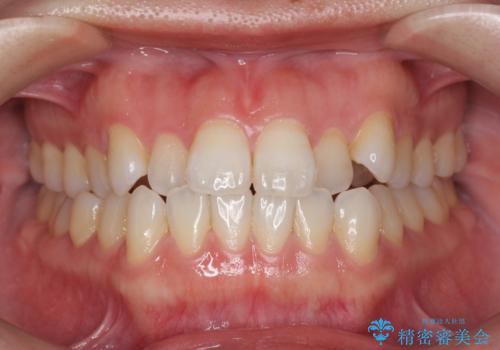

[ インビザライン ] 前歯のガタつきをマウスピース矯正で改善

![[ インビザライン ] 前歯のガタつきをマウスピース矯正で改善の症例 治療前](https://seimitsushinbi.jp/wp/wp-content/uploads/2023/06/C14-500x350.jpg?v=1686815742)